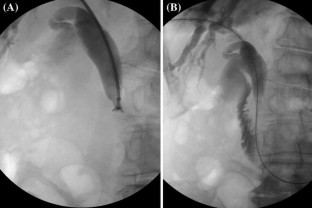

Fig. 1